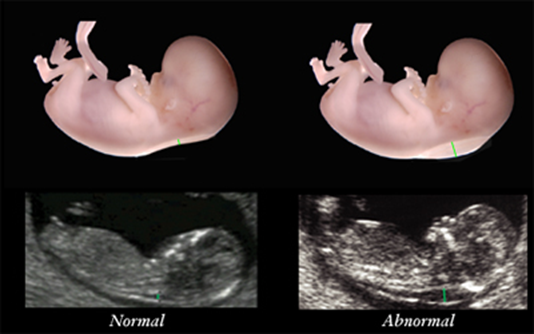

Fetal crown–rump length ‘CRL’ (bebeğin baş-popo mesafesi) minimum 45mm ve maximum 84mm olmalı.Fetal nuchal translucency ölçümü için en uygun zaman 11-13+6 hafta arasıdır.Bu dönemde yapılan ölçümlerin başarısı 98–100% dir, bu oran 14.hafata ve sonrasında 90% a düşer.Fetal pozisyon ölçüm yapılırken durumu güçleştirebilir.(özelikle vertikal pozisyon)Transabdominal ve transvaginal ölçümler arasında birbiriyle benzer sonuçlar elde edilmiştir ancak transvaginal uygulamanın daha iyi bir metodolduğu düşünülmektedir.Fetusun CRL sini doğru bir şekilde ölçebilmek için iyi bir sagital kesit yakalanması gerekmektedir.Ultrason cihazının iyi bir büyütmeye sahip olması ve 0,1mm ye kadar hassas kalibrasyonun olmalıdır.Fetusa ait deri tabakası ile amnion zarının çok iyi bir şekilde ayırt edilmesi gerekmektedir.Çünkü her ikisi de ince zar olarak görülür.Bunu başarmak için de fetusun hareket edip amniotik zardan uzaklaşmasını beklemek gerekir.Veya fetusun hareket etmesini sağlamak için anneye öksürmesi söylenir veya annenin karnına hafifçe dokunulur.Servikal omurgayı ötrem yumuşak doku ile cilt arasındaki maksimum kalınlık ölçülür.İnceleme esnasında birden fazla löçüm yapmak gerekir ve bunların en kalını kayda alınmalıdır. Ense kalınlığı ölçümü fetus nötral pozisyondayken yapılmalıdır.Fetusun başını arkaya attığı extensiyon pozisyonunda ölçüm 0,6mm fazla ,fetusun başını öne eğdiği flexion pozisyonda ise 0,4mm eksik olabilir. % 5-10 vakada göbek kordonu fetusun boynunun çevresinde olabilir ve ense kalınlığı ölçümünü 0,8 mm kadar artırabilir.

Fetal ense kalınlığı CRL (bebeğin boyu) ile uyumlu olarak artar.Yüzbin gebeliğin incelendiği bir çalışmada ,11.haftada ölçülen ortalama ense kalınlığı 1,2 mm den , 13+6 haftada 1.9mm ye yükselmiştir. Genel olarak ense kalınlığı (NT) 3mm den fazla olduğunda patolojik olarak kabul edilir.